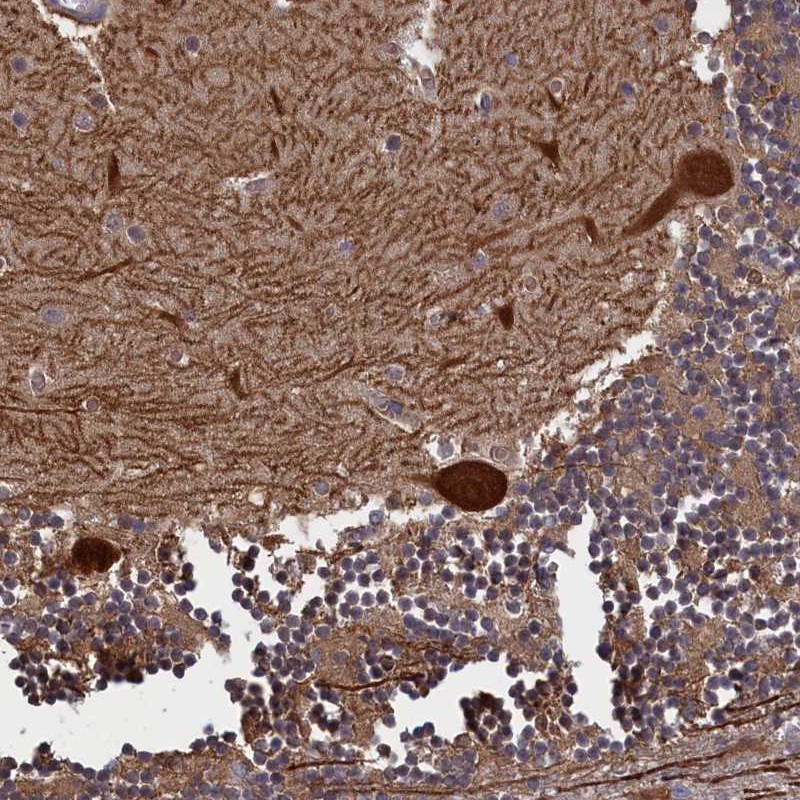

Immunohistochemical staining of human cerebellum shows strong cytoplasmic positivity in Purkinje cells.